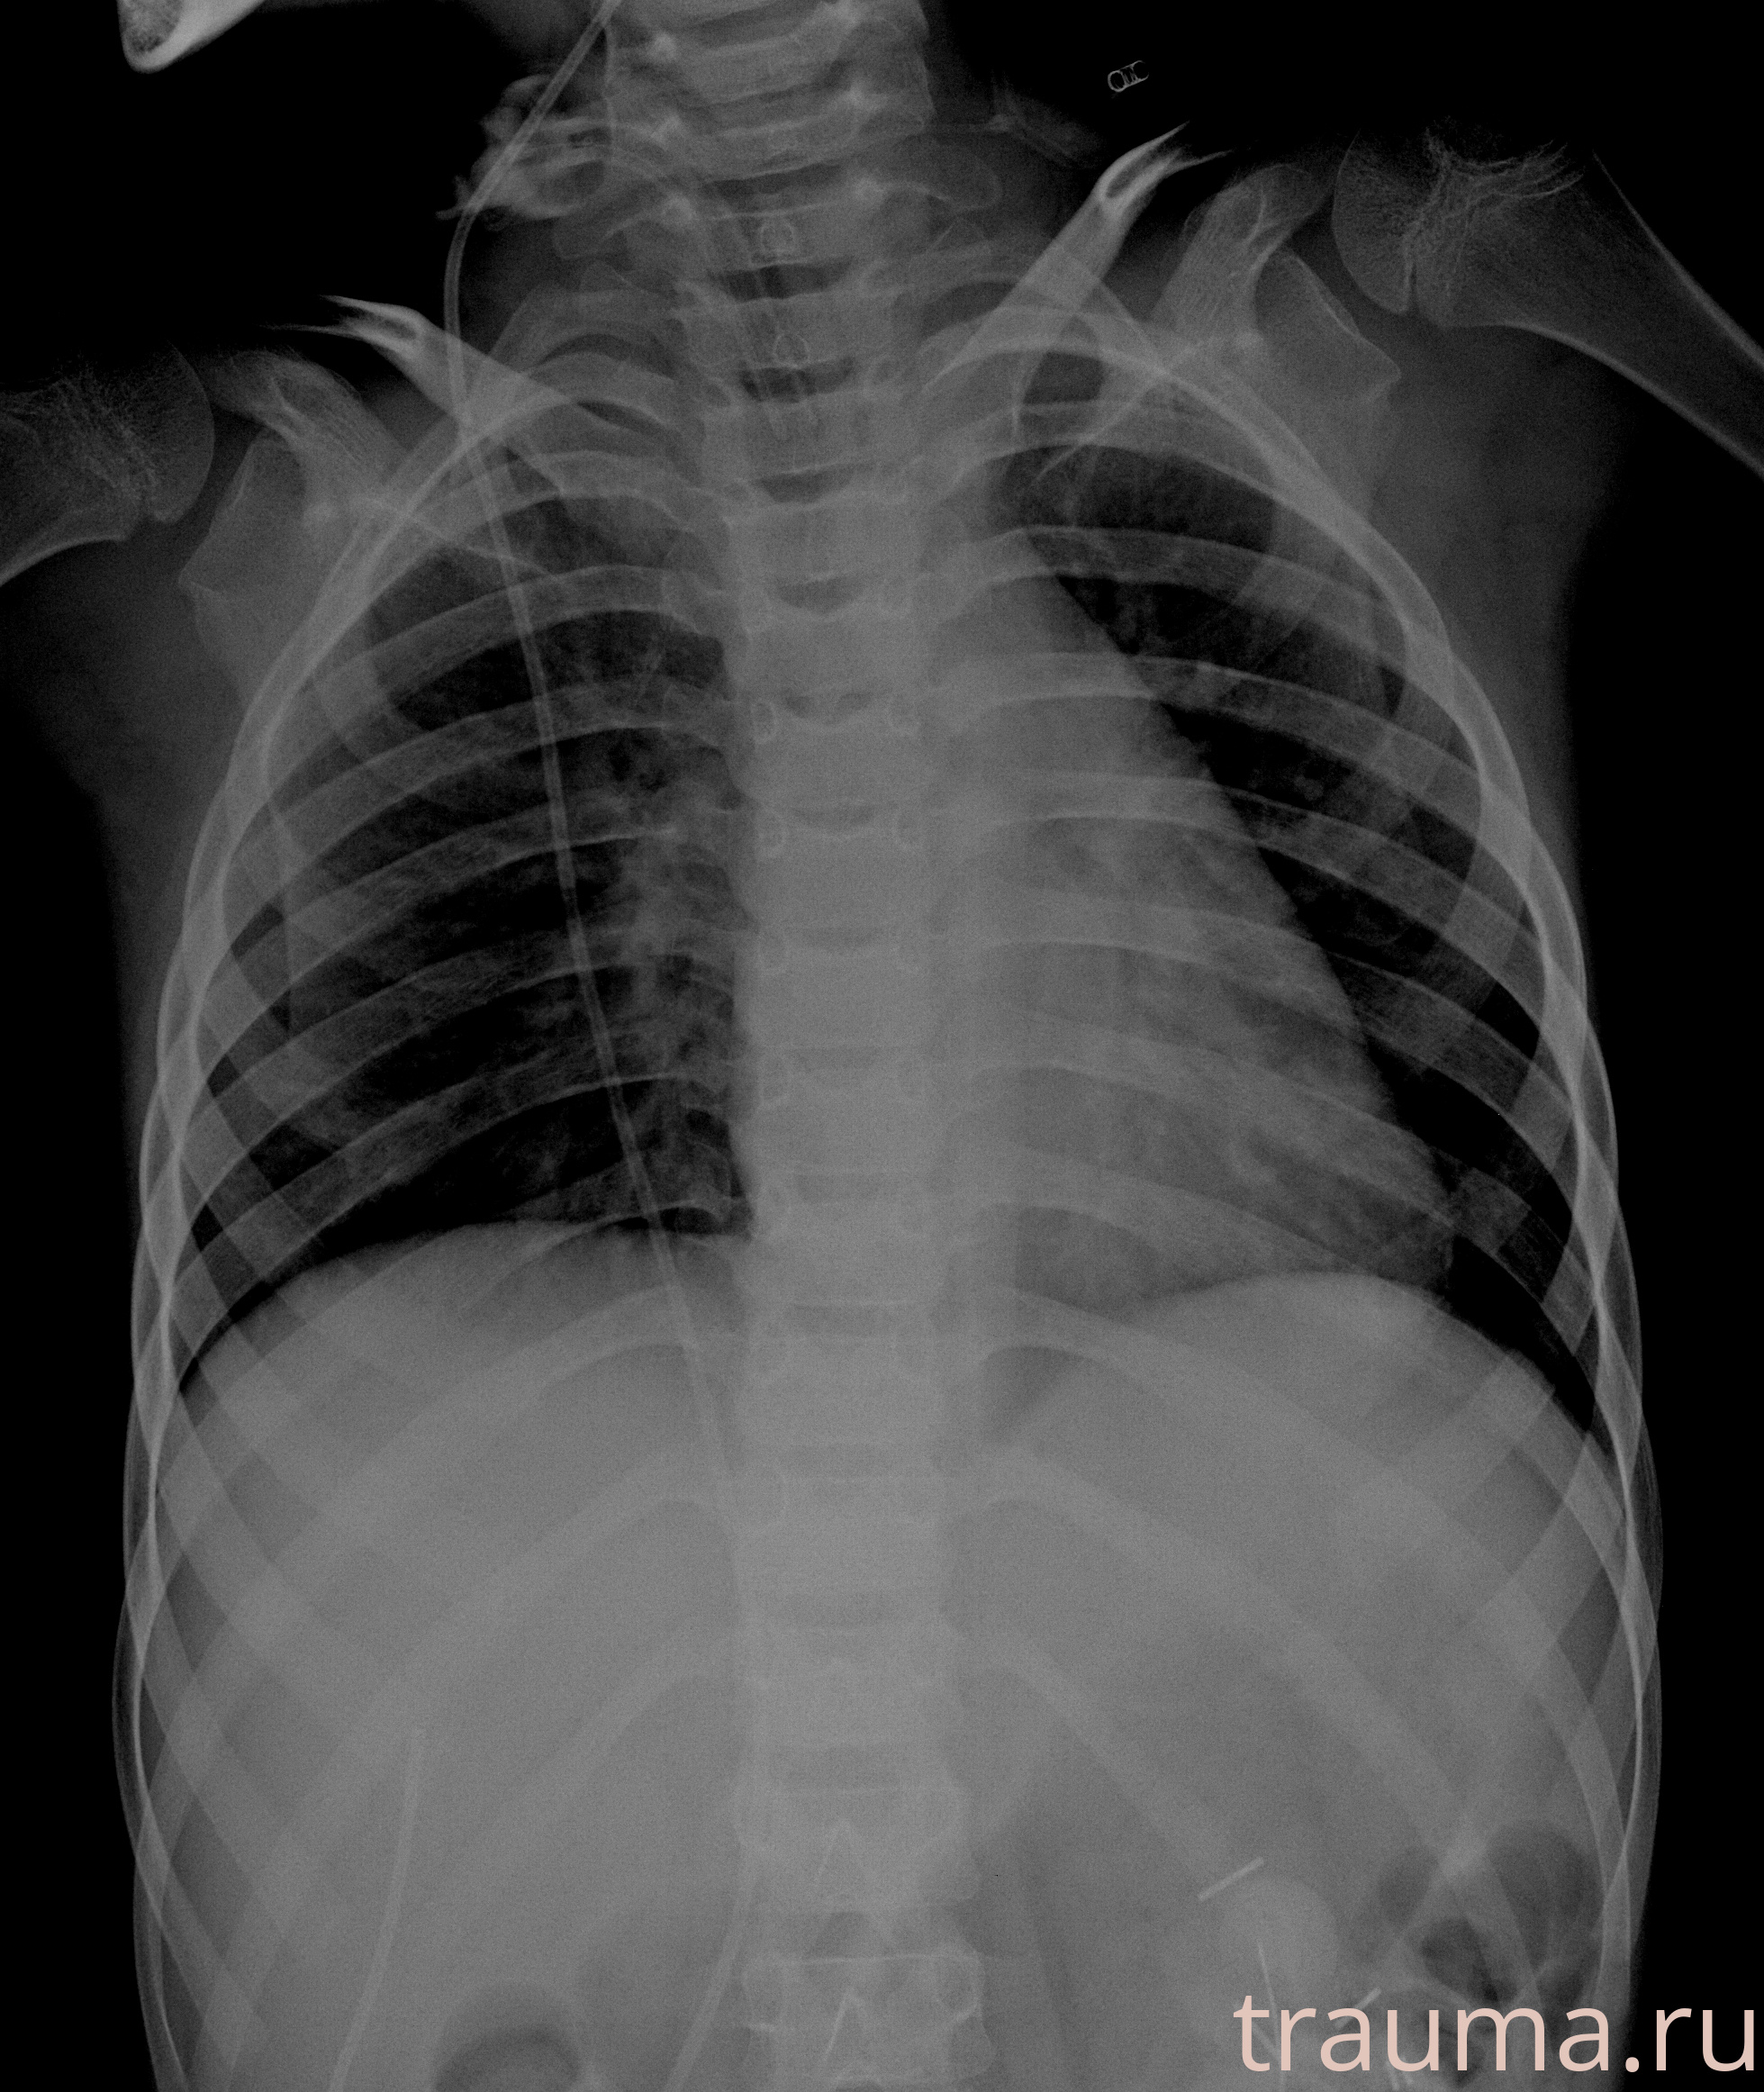

Рентгенограммы

Рентген на дому: по вашему адресу приезжает врач-рентгенолог, травматолог-ортопед с мобильным рентгеновским аппаратом, проводит диагностику травмы или заболевания, делает необходимые рентгенограммы, дает рекомендации по дальнейшему лечению. Получить качественные снимки в домашних условиях возможно благодаря уникальной методике, разработанной МосРентген Центром для института  Склифосовского

Яркость: 1   Контраст: 1   Инвертировать: 0 Увеличение: 1

Перетаскивайте мышь вверх/вниз для контраста, влево/право для яркости. Прокрутка колесом изменяет масштаб. Нажмите Сбросить для возврата к исходному изображению. При увеличении держите мышь в той области, которую хотите рассмотреть.

при переломе шейки бедра и пневмонии от компании МосРентген Центр - партнера Института имени Склифосовского